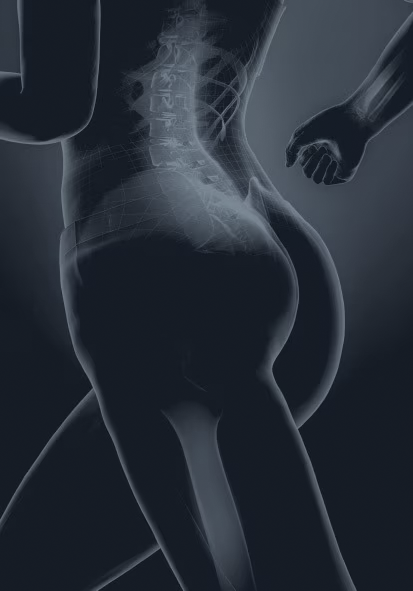

O PRIMUS é um sistema de densitometria óssea avançado, desenvolvido para fornecer análise detalhada da composição corporal e avaliação da densidade mineral óssea (DMO). Com tecnologia DXA de última geração, o PRIMUS oferece escaneamento de corpo inteiro de alta precisão, garantindo diagnósticos mais confiáveis em osteoporose, sarcopenia e obesidade.

O PRIMUS combina tecnologia avançada de absorciometria de raios X de dupla energia (DXA) com um design ergonômico, permitindo avaliações rápidas e precisas.

Tecnologia de escaneamento DXA

- Feixe em leque estreito otimizado, garantindo medidas mais precisas da densidade mineral óssea.

- Detectores multicanais, permitindo cobertura ampliada e maior velocidade de escaneamento.

- Alta resolução para análise morfológica esquelética, possibilitando estudos detalhados da estrutura óssea.

Aplicações clínicas avançadas

- Avaliação de DMO em corpo inteiro ou regiões específicas, permitindo diagnóstico precoce da osteoporose.

- Medição quantitativa de gordura, osso e massa magra, possibilitando acompanhamento nutricional e metabólico.

- Detecção e acompanhamento da sarcopenia, auxiliando na análise de perda de massa muscular.

- Análises avançadas de obesidade e lipodistrofia, facilitando diagnósticos e tratamentos personalizados.